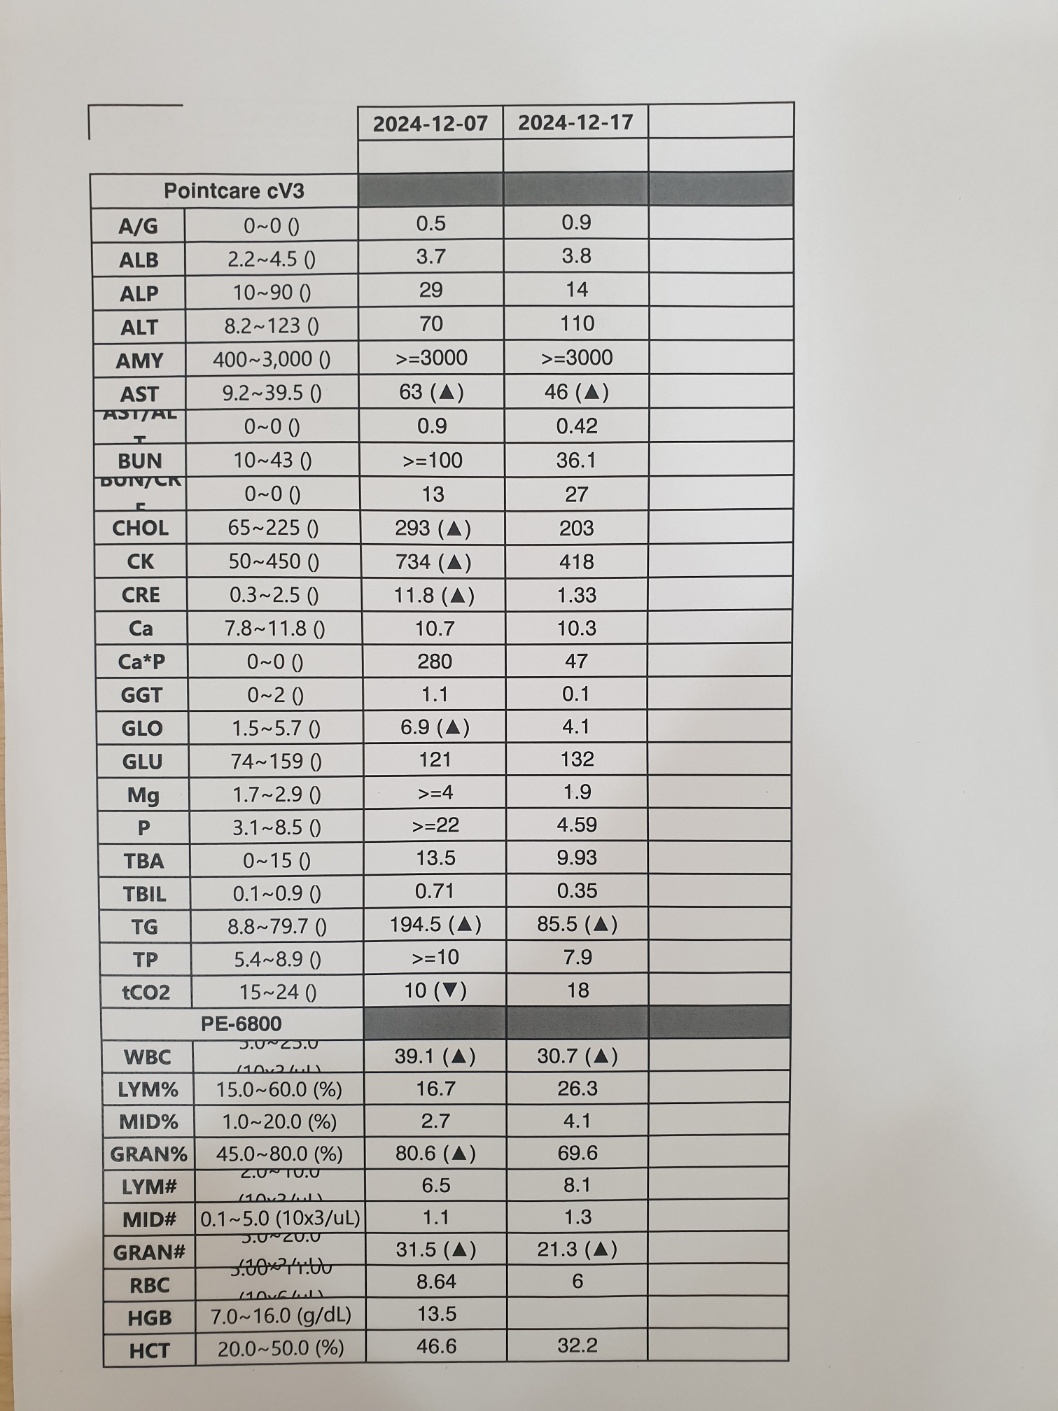

| 치료과정 | 2024년 12월 7일 토요일 오전에 피침을 흘리며 기력 없이 쓰러져 있던 동경이는 바로 병원으로 이동했습니다.. 12월 초부터 이상 징후가 있었던 동경이를 지켜보면서 혹시나 범백이 아닐까 의심스러웠던지라 의사 선생님께 그동안의 상황을 설명하고 범백키트 검사를 먼저 하였습니다.. 너무나도 다행스럽게 범백은 음성으로 나왔습니다 그동안 만약 범백이라면 밥자리에 있는 많은 아이들은 어쩌나 싶어서 정말 걱정이 되었거든요 너무 너무 다행스런 순간이었습니다.. 이후 엑스레이와 혈액검사를 진행 하였고 엑스레이 결과 위장 내용물이 한개도 없었다는..ㅠ ㅠ 그동안 전혀 먹지를 못했다는 것이었지요 얼마나 아프고 힘들었을지 .. 동경이 한테 너무 미안 했습니다 며칠이라도 빨리 병원에 데리고 왔으면 덜 고생 했을텐데.. 미안하고 또 미안 했어요 .. 모든 검사결과 신장이 거의 두배로 부어있었고 혈액검사도 신장수치와 췌장수치를 포함한 모든 수치가 많이 높게 나왔습니다 선생님께서 급성신부전으로 진단하시고 바로 수액처치와 필요한 치료에 들어갔습니다.. 입원 이틀동안은 자발식이가 전혀 없어서 걱정스러웠는데 삼일째 드디어 동경이가 먹기 시작했습니다.. 입원 삼일째부터 동경이는 그동안 굶은것을 만회 하는것처럼 너무 너무 잘 먹어주었습니다 매일 매일하는 링거치료도 잘 견뎌주고 착한 아이라고 선생님께 칭찬도 많이 받았어요..ㅎㅎ 저를 보면 반가움의 인사가 비록 하악질로 시작 됐지만 잘 이겨내고 서서히 회복해가는 동경이를 얼마나 기쁘고 감사하던지 .. 의사 선생님께서 입원 치료중 중간 시점에 혈액검사를 권하였지만 검사 자체가 동경이 한테 큰 스트레스가 될수 있으니 며칠 더 치료후 검사를 해달라고 했고 드디어 12월 17일 혈액검사를 했습니다.. 피 뽑고 결과를 기다리는데 어찌나 떨리던지 ..ㅠ 검사 결과 동경이의 신장을 포함한 모든 수치가 정상으로 나왔고 퇴원이 가능해졌습니다 |